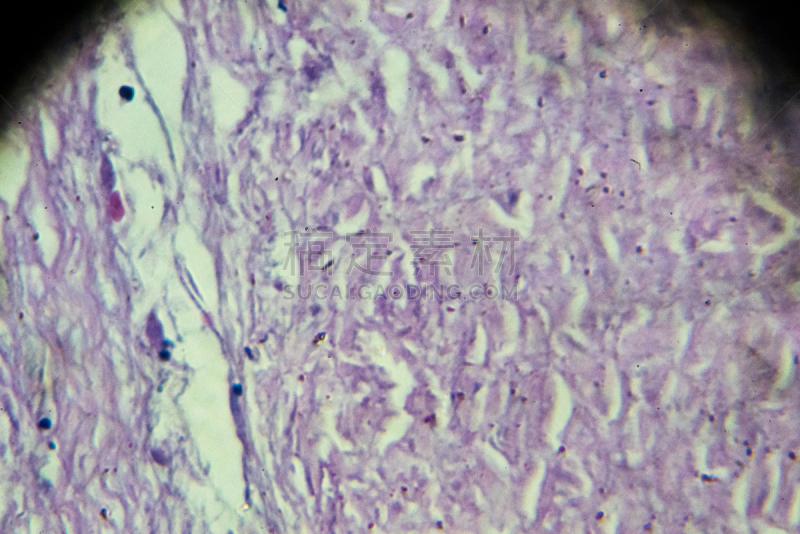

人体组织的组织学详情